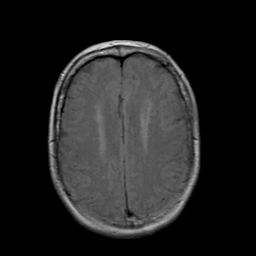

Stroke: proton density-weighted MR #2 -- Slice #17

[Home][Help][Clinical] Slice 17